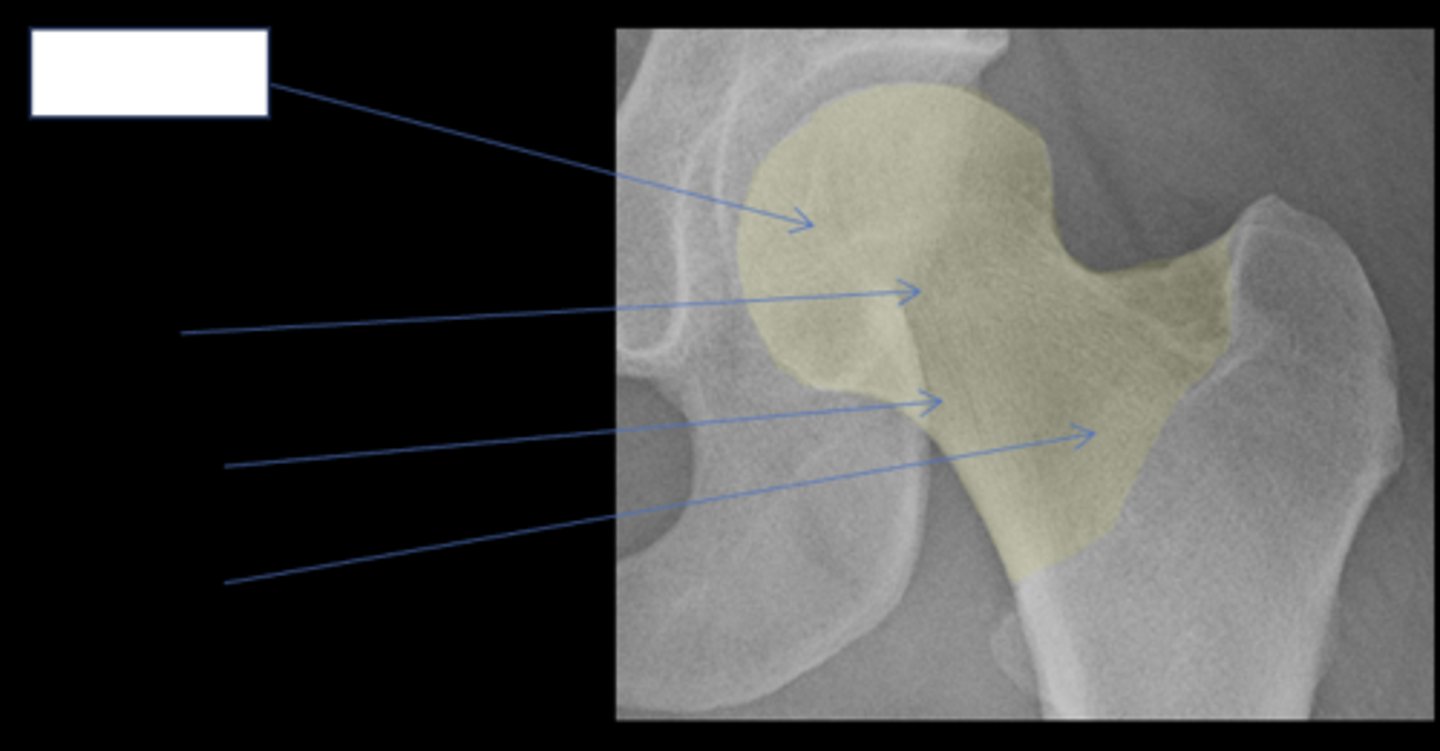

Hip joint space width

ID measurement

<p>ID measurement</p>

Superior, axial, medial joint spaces (SAM)

Hip joint space width landmarks

<p>Hip joint space width landmarks</p>

3-6 mm

Normal superior hip joint space width

<p>Normal superior hip joint space width</p>

3-7 mm

Normal axial hip joint space width

<p>Normal axial hip joint space width</p>

4-13 mm

Normal medial hip joint space width

<p>Normal medial hip joint space width</p>

Joint effusion

Clinical significance of a wide hip joint space

<p>Clinical significance of a wide hip joint space</p>

Arthritis

Clinical significance of a narrow hip joint space

<p>Clinical significance of a narrow hip joint space</p>